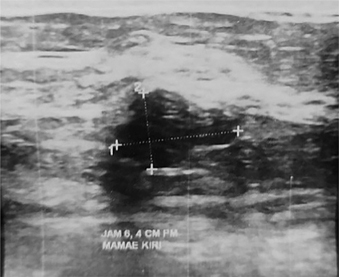

Sonographic BI-RADS findings should be correlated with the previous mammography results. Tissue composition reporting which consists of echogenicity of breast tissue parenchyma (using fat tissue as the comparison) is parallel with the findings on mammogram. For instance, homogenous echotexture-fibroglandular is parallel with extremely dense tissue on mammogram. Inversely, heterogenous echotexture of fat will be parallel to heterogenous density. Masses observed on US should also be compared with mammogram, even though different mass descriptor index is used, for example, oval, round, or irregular on mammograph, which is not the case with US. In US, margin description may assist in determining malignancy (Figure 3). Angular margin (which is unique to US), micro-lobulated, or spiculated findings may suggest non-benign diagnosis, although it is not a confirmation. Calcifications, which are neatly described in either mammogram or MRI, are not typically screened on US. However, findings of intraductal calcification should be considered as a suspicious mass, and further confirmation on mammogram or even core biopsy is highly indicated (63, 64).

Fig 3

Figure 3. Irregular shaped mass with ill-defined margins on US imaging, suggested for malignant diagnosis of breast neoplasm. Image provided by Division of Oncology, Department of Surgery, Faculty of Medicine, Universitas Sumatera Utara.